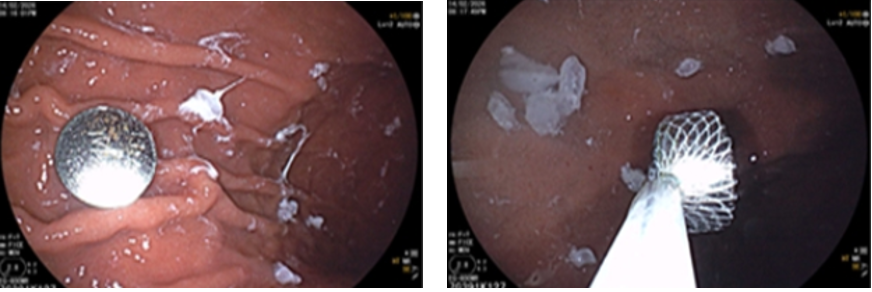

Trong lúc gia đình dọn dẹp, đón khách đến chơi, bé V.Q.T (9 tuổi, Hà Nội) đã vô tình nuốt phải pin cúc áo – loại pin thường có trong đồ chơi, điều khiển từ xa hoặc đèn trang trí.

Gia đình phát hiện kịp thời và đưa bé đi khám ngay. Kết quả chụp X-quang phát hiện dị vật trong ổ bụng.

Nội soi dạ dày xác định pin trong dạ dày và đã lấy ra an toàn

Điều đáng lo ngại là pin cúc áo có thể gây bỏng hóa chất rất nhanh, chỉ sau vài giờ, làm tổn thương nghiêm trọng thực quản hoặc dạ dày. Nhiều trường hợp trên thế giới đã ghi nhận biến chứng nặng do xử trí muộn.